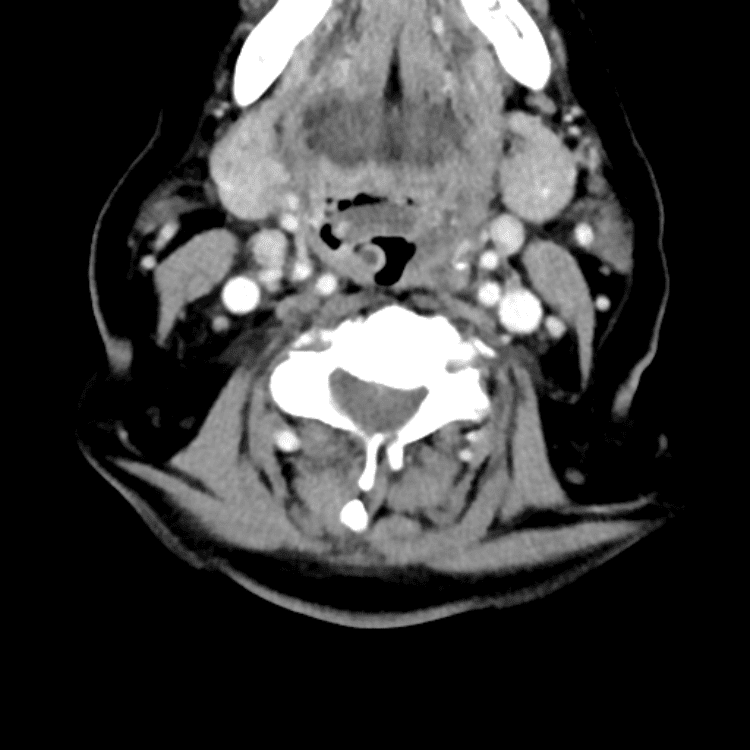

Head and Neck

Practice

Simulates call by including subtle or difficult cases and some normals.

27 cases